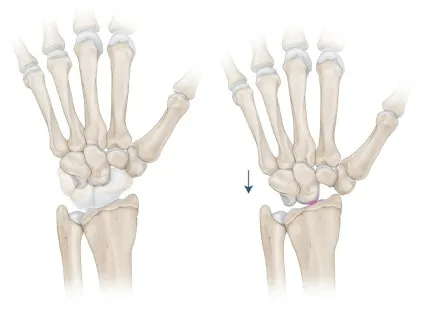

- Proximale rijresectie: In bepaalde situaties kan een proximale rijresectie worden uitgevoerd. Hierbij wordt de eerste rij van drie handwortelbeentjes verwijderd. De pols scharniert nadien in één enkel gewricht in plaats van in twee gewrichten. Deze ingreep laat nog een zekere graad van beweeglijkheid toe, meestal ongeveer de helft van een normaal polsgewricht (dit wil zeggen ongeveer 45° plooien en strekken).